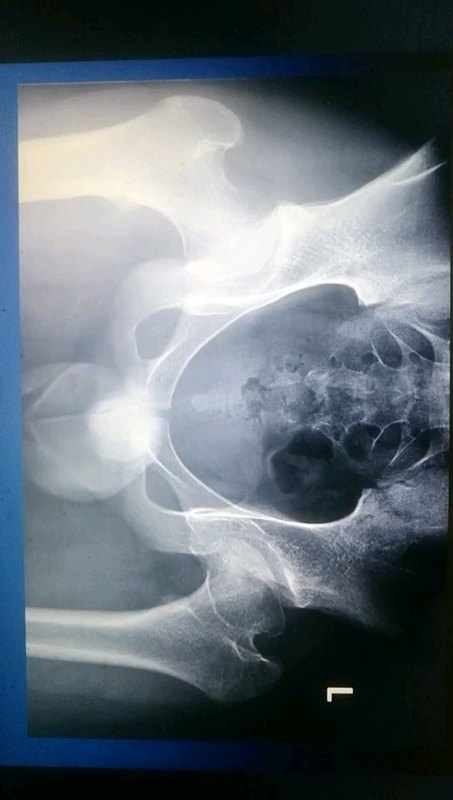

Perthes 病科普系列之二:儿童股骨头坏死如何分期

张中礼主任医师 天津医院 小儿骨科

3338人已读